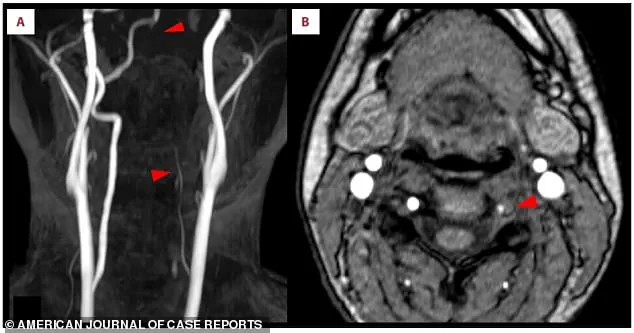

Doctors identified a tear in the inner lining of her left vertebral artery, a condition known as vertebral artery dissection (VAD).

This tear allowed blood to seep into the artery wall, forming a clot that narrowed the passageway.

Further investigation revealed a crescent-shaped blood clot embedded within the left vertebral artery, a vital conduit for blood to reach the brain.

This artery, visible in the scans, appeared faint and thin, signaling restricted blood flow.